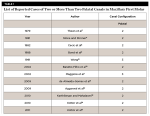

A brief review of recent case reports of extra palatal root canals in maxillary first molars is presented in Table 1.

The operator’s ability to find additional canals is improved with adequate knowledge and experience to find additional canals, especially in the maxillary molars.6 Endodontic literature states that the maxillary first molar consists of 3 roots with 3 or 4 root canals.1 The prevalence of maxillary first molars with two palatal canals is rare. Thews et al,7 Stone and Stroner,4 Cecic et al,8 Bond et al,9 Baratto-Filho et al,10 de Almeida-Gomes et al,11 Aggarwal et al,12 Karthikeyan and Mahalaxmi,13 and Kottor et al14,15 have reported cases with 2 palatal canals, whereas Wong16 and Maggiore et al1 have described teeth with 3 palatal canals. This report highlights a maxillary left first molar with 2 palatal canals. The variable shape of the pulp cavity makes every treatment unique. Properly designed and prepared access cavities help the clinician diagnose and negotiate the root canal anatomy. In the present case, the conventional triangular access was modified into a trapezoidal form to improve access to the additional canals. Usually, the reading of a radiograph along with a careful inspection of the pulp chamber floor by probing and proper visualization enables the operator to locate and identify the root canal orifice. The use of endodontic explorer, surgical loupes, and electronic apex locator were crucial both for the detection and management of the 2 canals in the palatal and mesiobuccal roots. Clinician should thoroughly examine the pulpal floor and radiographs for the possibility of additional canals.